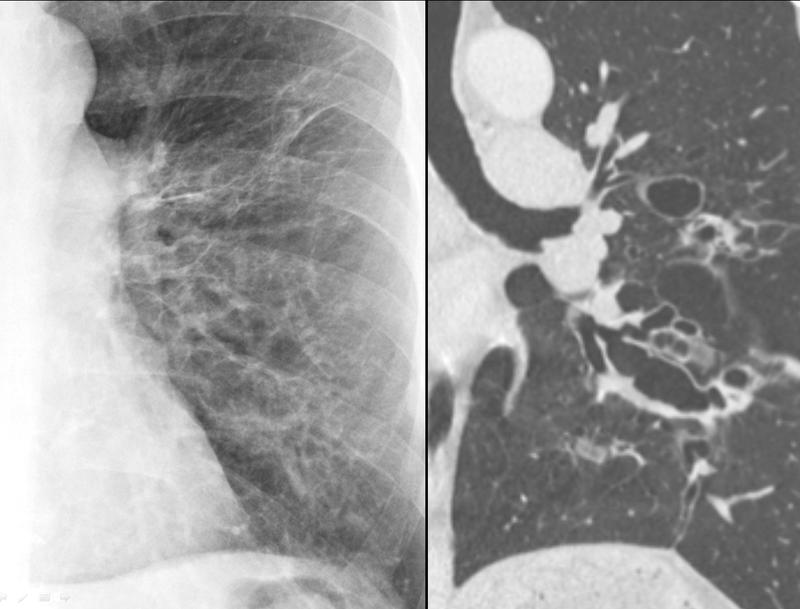

Bronchiectasis with coronal CT